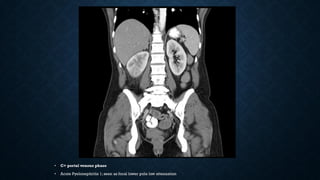

• C+ portal venous phase

• Acute Pyelonephritis 1; seen as focal lower pole low attenuation

• Contrast-enhanced CT of the kidneys demonstrates a striated paflern in the kidneys in

the nephrographic phase.